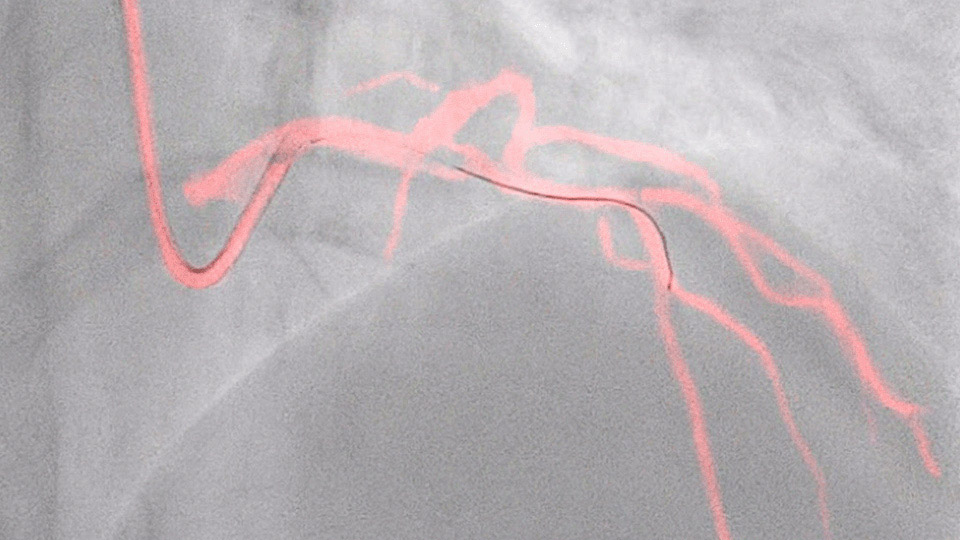

This Philips-exclusive technology provides a real-time view of the coronary arteries and removes the need for additional contrast injections.

New data shows that Philips Dynamic Coronary Roadmap has the potential to reduce the use of contrast agent during PCI procedures by 28.8%

New invasive imaging techniques and co-registration software allows PCI to be performed with limited amounts of contrast, even with zero-contrast use, to reduce the risk of CI-AKI for all patients, and especially those with renal insufficiency.

Philips PCI guidance solutions incorporate non-invasive and adjunctive IVUS and iFR modalities, requiring less contrast for proper diagnosis.